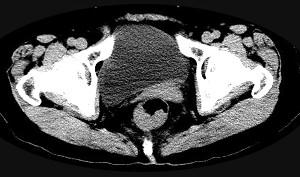

问题 男,56岁,排便形状改变,便不尽感,CT检查如图所示,下列说法正确的是 ( )

选项 A、此为直肠息肉 B、此为直肠癌 C、其表面光滑,边界清楚 D、肠腔未见狭窄 E、肠壁上有蒂状新生物 单选题

答案 B